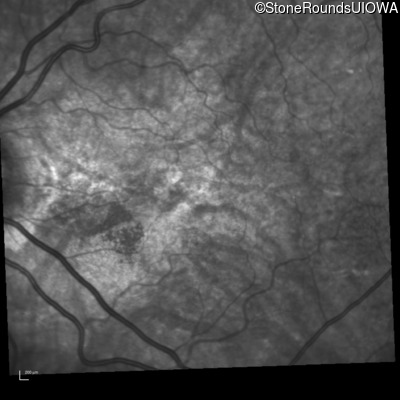

Infrared Fundus Photograph - Right - 20/20 -3 sc

Exemplar